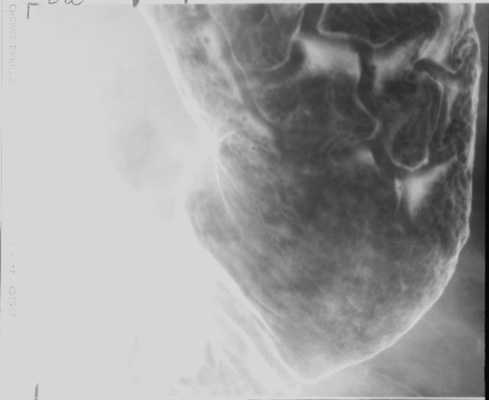

- Gastric antrum (patient LPO)